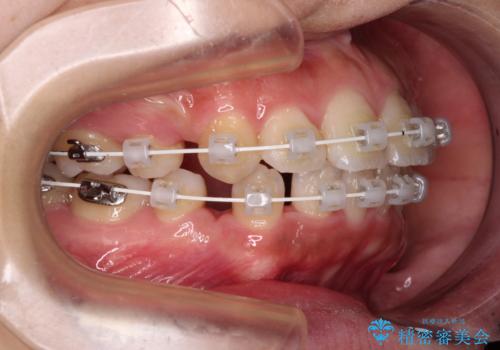

- 矯正装置

- 審美装置

- 2年1ヶ月

- 10-30回